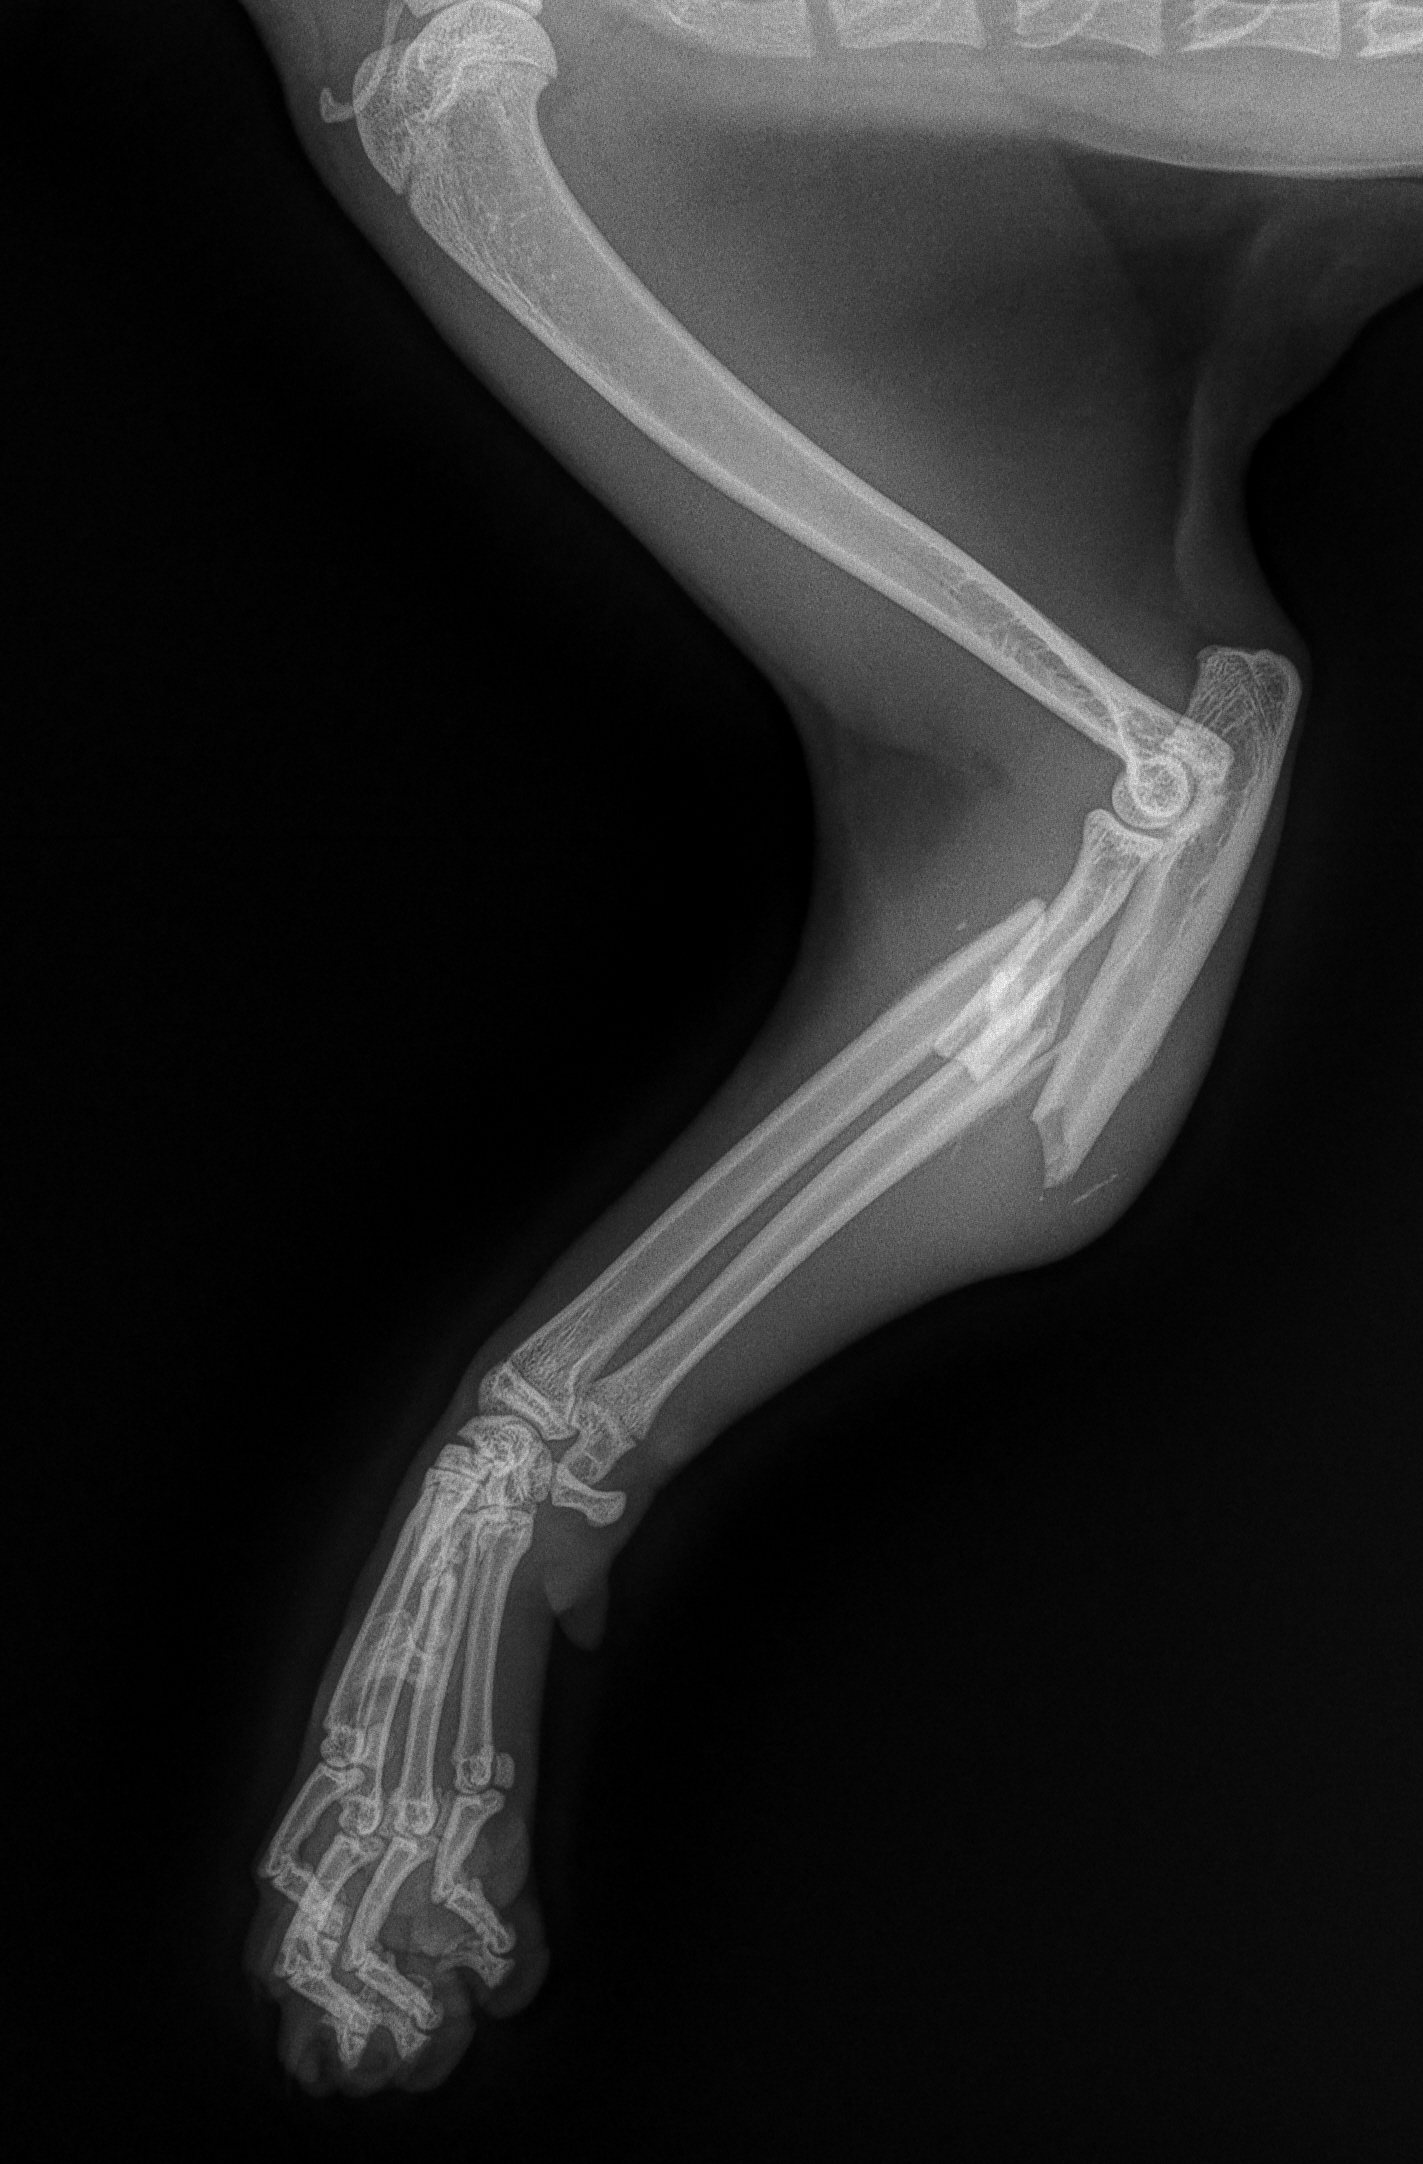

Wykonujemy stabilizację stawu kolanowego u zwierząt z przerwanym lub częściowo uszkodzonym więzadłem krzyżowym przednim metodą TTA RAPID, CWO oraz metodą szwu bocznego.

Uszkodzenie więzadła krzyżowego przedniego stawu kolanowego